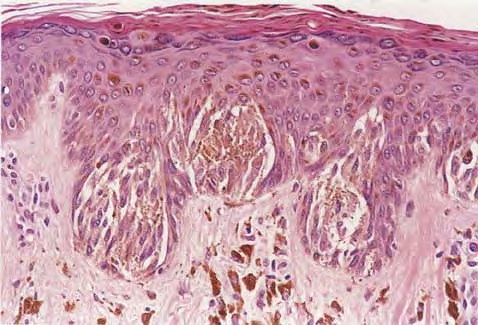

The lesions are usually 3 to 6 mm in diameter, deeply pigmented, and either flat or slightly raised. Most patients are young adults, and the most common location is on the lower extremities. Pigmented spindle cell nevi are uncommon after the age of 35 years. A classic presentation is that of a newly evolved black plaque on the thigh of a young woman. Because of the heavy pigment and the history of sudden appearance, a diagnosis of melanoma is often suspected clinically. In contrast, Spitz nevi are usually submitted with a benign clinical diagnosis, such as an angioma or a dermal nevus. Like Spitz nevi, the lesions are generally stable after a relatively sudden appearance and a short-lived period of growth. Histopathology. The pigmented spindle cell nevus is characterized by its relatively small size and its symmetry and by a proliferation of uniform, narrow, elongated, spindle-shaped, often heavily pigmented melanocytes at the dermal-epidermal junction . The nests of spindle cells are vertically oriented and tend to blend with adjacent keratinocytes rather than forming clefts as in Spitz nevi. Eosinophilic globules (Kamino bodies) may be present . The tumor cells often form bundles that are separated by elongated rete ridges. In the papillary dermis, the nevus cells lie in compact clusters, pushing the connective tissue aside. Numerous melanophages are characteristically diffusely present within the underlying papillary dermis. Involvement of the reticular dermis, common in Spitz nevi, is unusual in pigmented spindle cell nevus. Some lesions show upward epidermal extension of junctional nests of melanocytes. Single-cell upward invasion of the epidermis in a pagetoid pattern may be present but is usually not prominent . Features that may lead to a diagnosis qualified as atypical pigmented spindle cell nevus include architectural abnormalities including poor circumscription and pagetoid melanocytosis, prominent cytologic atypia, or a prominent epithelioid cell component . There may also be considerable overlap with dysplastic nevi . The significance of these atypical variants appears to lie in their greater chance of being misdiagnosed as melanoma because all reports of pigmented spindle cell nevi emphasize their benign behavior after excision. |